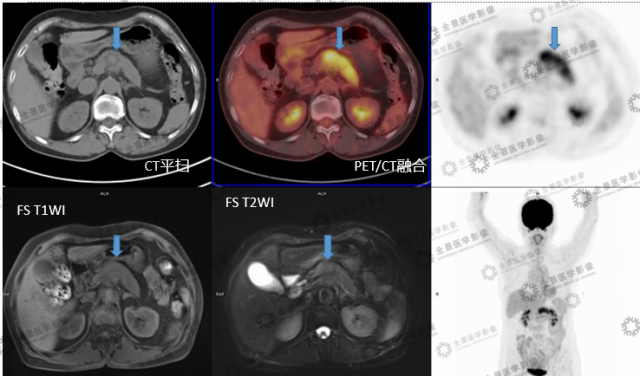

实例一

病史:女 70 岁 腹部不适,纳差半月,CT:胰腺 MT 伴小网膜囊淋巴结肿大及血管侵犯。

病灶呈延迟强化,FDG 代谢增高,考虑胰腺癌。